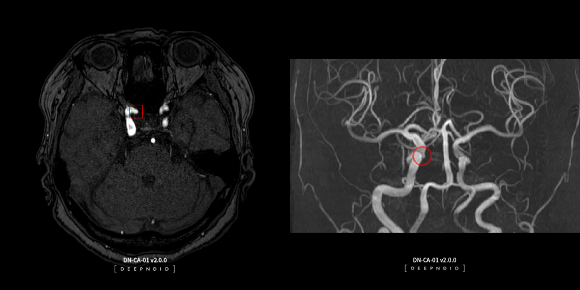

딥노이드는 AI설루션 개발에서부터 배포, 활용 등의 AI영상진단 전 과정에서 생태계를 구축하고 있다.직접 AI설루션을 개발하는 파이프라인 방식뿐만 아니라 의료인이 AI설루션을 개발할 수 있도록 돕는 플랫폼 방식의 '투트랙' 사업모델을 운영하고 있다. 이 중 플랫폼 방식은 회사 내부 개발비용을 줄일 수 있는 장점이 있다. 현장의 수요(니즈)를 반영해 동시에 여러 설루션 개발을 추진할 수 있어 국내 AI영상진단기업 중 식약처로부터 가장 많은 설루션 품목허가를 받았다.

뇌혈관, 폐, 척추, 흉부, 유방 등 다양한 질환영역에서 18종의 AI설루션이 출시됐는데 경희의료원, 부산대학교병원 등 주요 대학병원은 물론 심평원에도 AI설루션을 공급하고 있다. 특히 심평원은 AI영상 저장 및 전송시스템 구축에 딥노이드의 AI영상 판독지원 설루션 딥팩스를 활용 중이다.

딥노이드는 AI영상진단 기기를 사용하는 현직 의사들을 AI설루션 개발에 참여시키며 AI영상진단 전 과정에서 생태계 구축 및 선점에 나서고 있다. 사진은 딥노이드의 뇌동맥류 뇌영상검출·진단보조 AI설루션 딥뉴로 운영화면. /사진=딥노이드